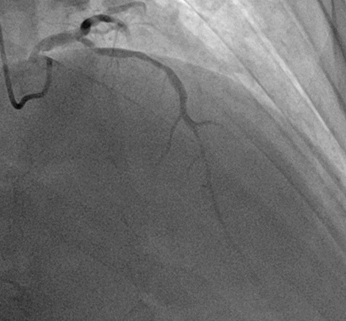

Los hallazgos fueron los siguientes:

· Tronco coronario izquierdo sin lesiones angiográficas significativas; descendente anterior (DA) estenosis severa entre tercio proximal y medio, suboclusiva; estenosis tercio distal coronaría derecha sin lesiones angiográficas significativas. (Ilustración 3 y 4).

Ilustración 3 Arteriografía coronaria derecha

Fuente: Hospital de Especialidades Guayaquil “Doctor Abel Gilbert Pontón”.